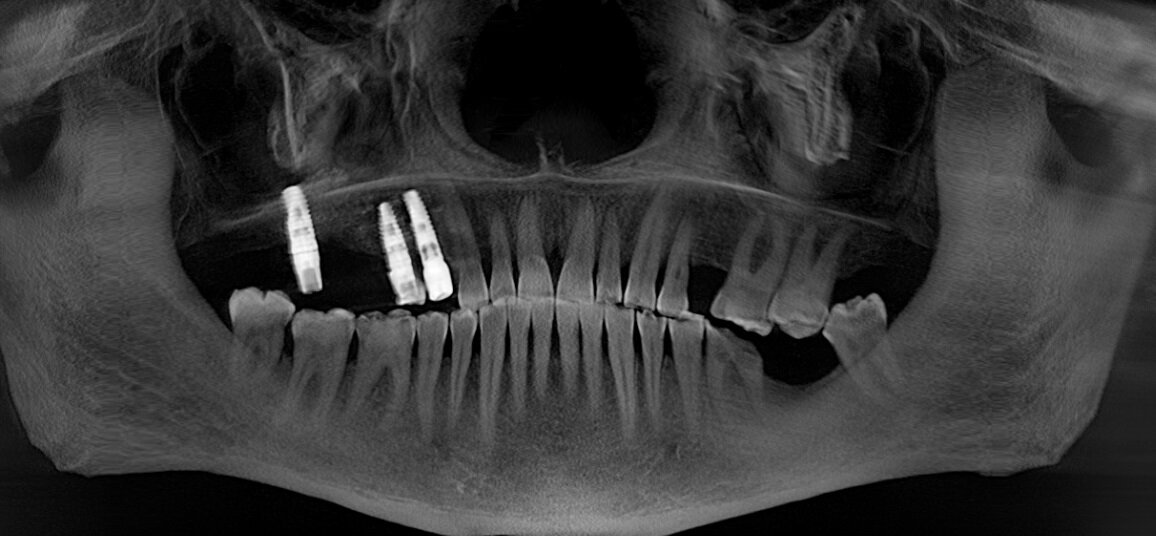

Первым контрольным рентгеновским снимком был этот:

На установленных ранее имплантатах в области 5 и 7 зубов на верхней челюсти справа (на снимке слева) стоял временный мостовидный протез. Пластик, из которого изготовляются временные конструкции не рентгеноконтрастен. Поэтому ничего кроме «белых полосок» в этой области вы не увидите. Средний срок службы подобных конструкций три месяца, но «по семейным обстоятельствам» пациент пользовался ими дольше обычного. Это привело к тому, что мостовидный протез треснул, аки старый трухлявый деревенский мост. В связи с этим, собственно, пациент и явился на прием. Напомню название статьи – «бруксизм». Сложно не заметить отсутствие зубов на противоположной стороне челюстей. Отсюда можно сделать логичный вывод, что основное (если не единственное) пережевывание пищи осуществлялось на стороне, где установлены имплантаты.